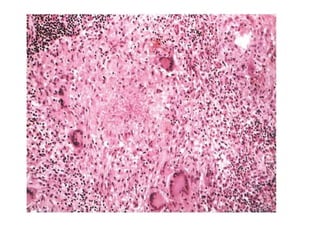

A granuloma is a focus of chronic inflammation

consisting of a microscopic aggregation of

macrophages that are transformed into epithelium-

like cells, surrounded by a collar of mononuclear

leukocytes, principally lymphocytes and occasionally

plasma cells

Epithelioid cells fuse to form giant cells in the periphery or

sometimes in the center of granulomas. These giant cells may

attain diameters of 40 to 50 μm. They have a large mass of

cytoplasm containing 20 or more small nuclei arranged either

peripherally (Langhans-type giant cell) or haphazardly (foreign

body–type giant cell). There is no known functional difference

between these two types of giant cells